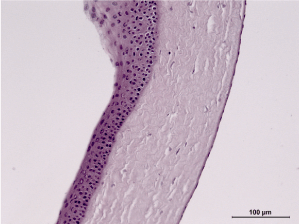

30th day – control group (B): abundant vascular ingrowth in the anterior layers of the cornea, formation of a vascular cataract, persistent swelling of the stroma. Hematoxylin and eosin dye, observed at 100x magnification. (Figure 22)

Figure 22. 30th day – control group (B).